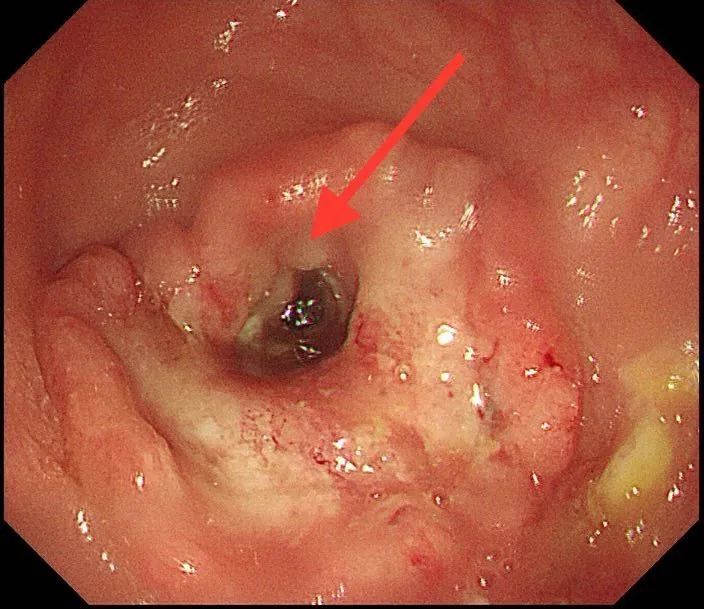

肠镜照片